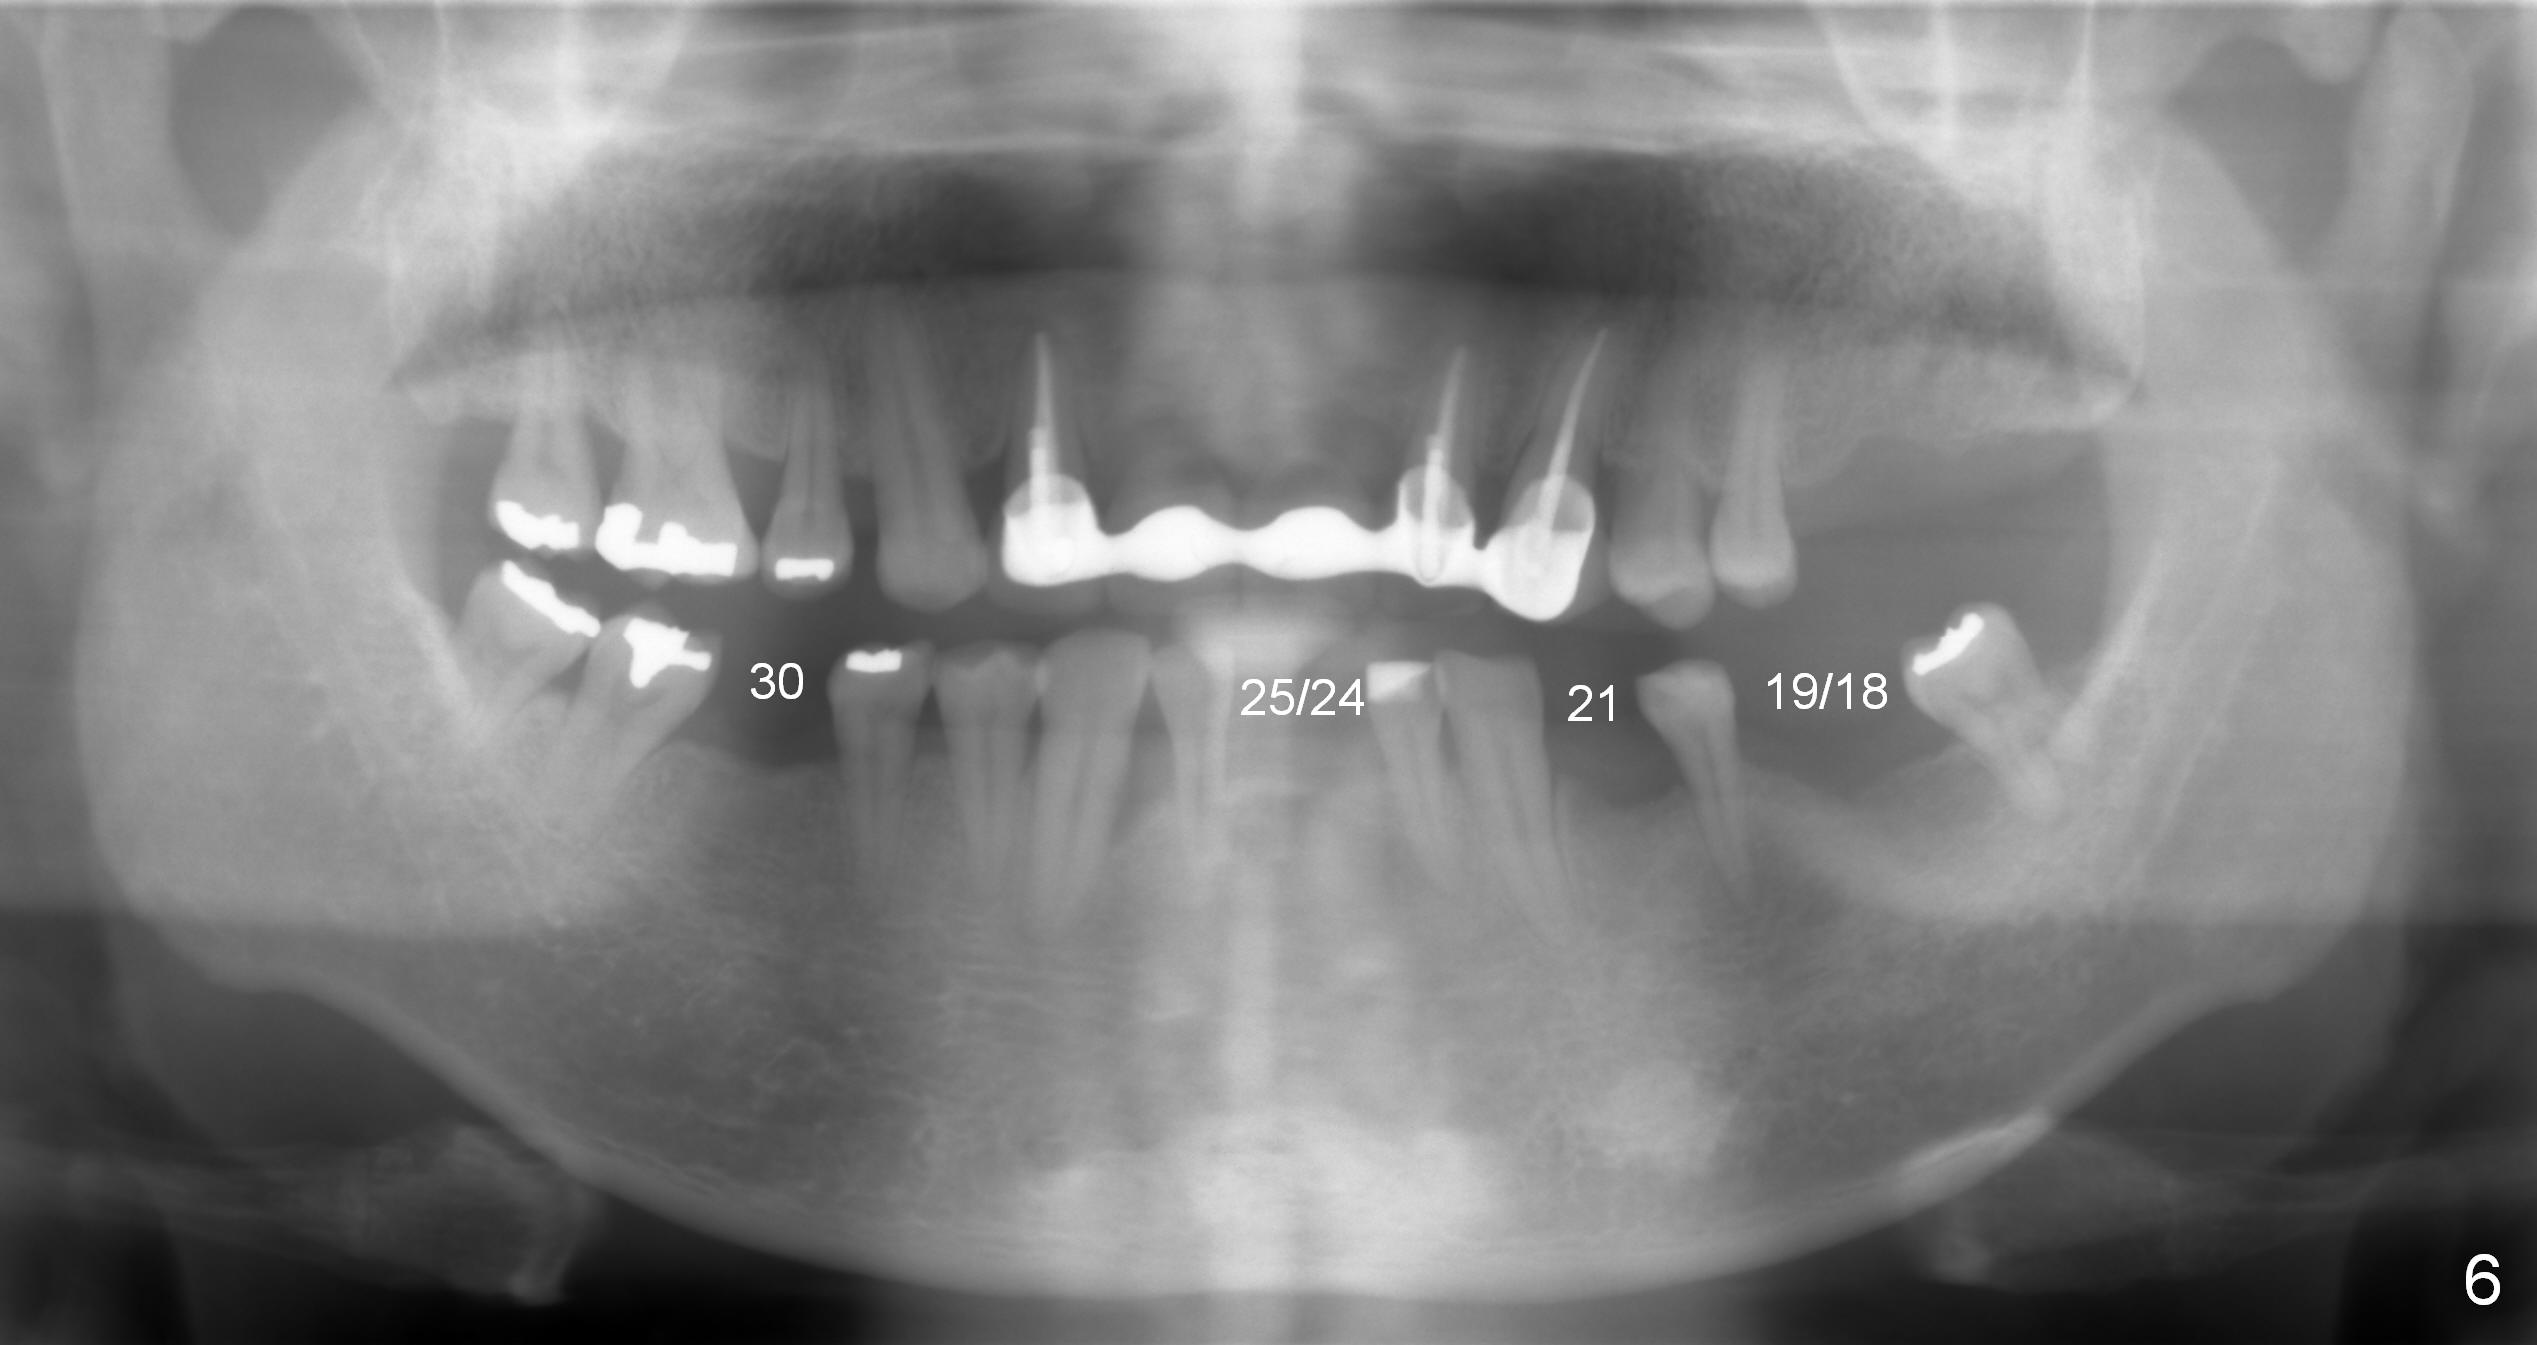

A 52-year-old man has multiple missing teeth. Since he has a lower partial denture (Fig.5), implants will be placed at the sites of #14 and 15 first (Fig.1). The site of #14 may need bone expansion if bone density is low, whereas the ridge at #15 is wide (Fig.2). There is no problem in height at the sites of #14 and 15 (Fig.3).

The buccolingual width at the sites of #19 and 21 appears narrow (Fig.4). On the other hand, the mesiodistal width at #19 seems to be wider than one molar and narrower than two (Fig.4-6). If CBCT and/or surgery confirms that the buccolingual bony width is narrow, two small diameter implants will be placed with restoration of two bicuspids.